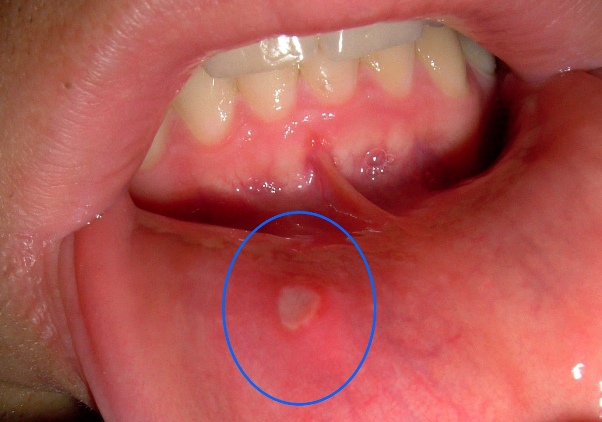

Afte su obično bijele ili žute boje s crvenim rubovima i mogu varirati u veličini. Ove ranice se najčešće pojavljuju na unutrašnjoj strani usana, obrazima, jeziku ili u dnu usne šupljine. Mogu trajati od nekoliko dana do dvije sedmice, a nakon toga se obično zacjeljuju bez ožiljaka. Iako ne predstavljaju ozbiljno zdravstveno stanje, njihovo prisustvo može znatno umanjiti kvalitetu života. U ovom članku ćemo istražiti uzroke afti, njihove simptome, te prirodne tretmane koji mogu pomoći u ublažavanju nelagode.

3. **Pojava ranica**: Obično se javljaju kao bijele ili žute ranice s crvenim rubovima unutar usne šupljine. Ove ranice mogu varirati u veličini, a neke osobe mogu imati više afti u isto vrijeme.